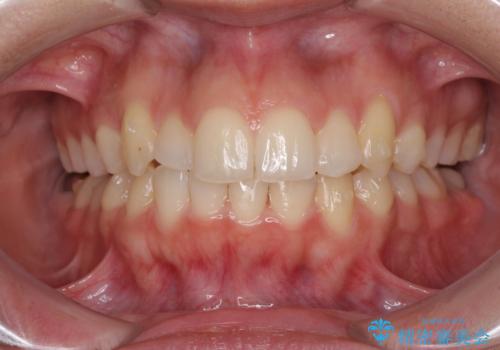

骨格的に左右にずれいている 前歯のデコボコをインビザラインで解消

叢生の程度は中等度であったため、IPR(歯と歯の間を削る)と歯列の側方拡大をメインに、インビザラインを用いて歯列を改善することとしました。

右側の咬合改善を目標に様々な手法を用いましたが、骨格的なズレによる不正咬合はインビザラインでは改善することができませんでした。